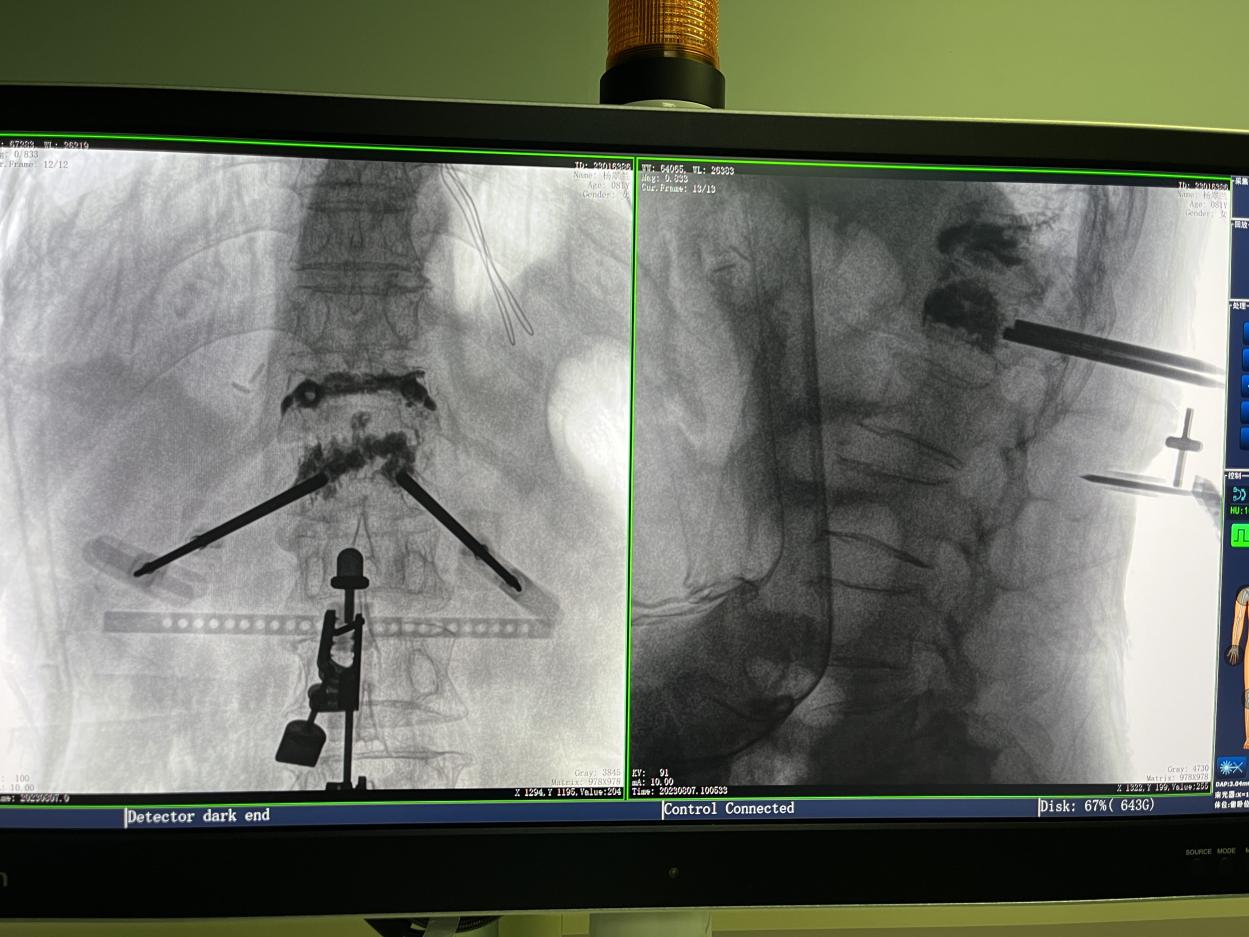

PL300B搭配普愛醫療自主研發生產的平板三維C形臂使用,通過三維立體術中圖像,手術醫生可從各個方位觀察合適的手術入路,并進行關鍵數據測量,從而最大限度地避開危險區。

骨科機器人手術-術中影像